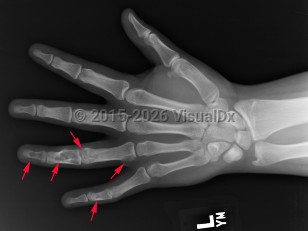

Ollier disease and Maffucci syndrome are nonhereditary conditions that present as multiple enchondromas. Ollier disease involves multiple asymmetric enchondromas of the digits. It is most commonly seen in childhood. These slow-growing tumors usually stop growing after puberty, but masses can create deformity and limb asymmetry. Pathologic fractures may be seen. Ollier disease has a 15%-20% risk for secondary chondrosarcoma.